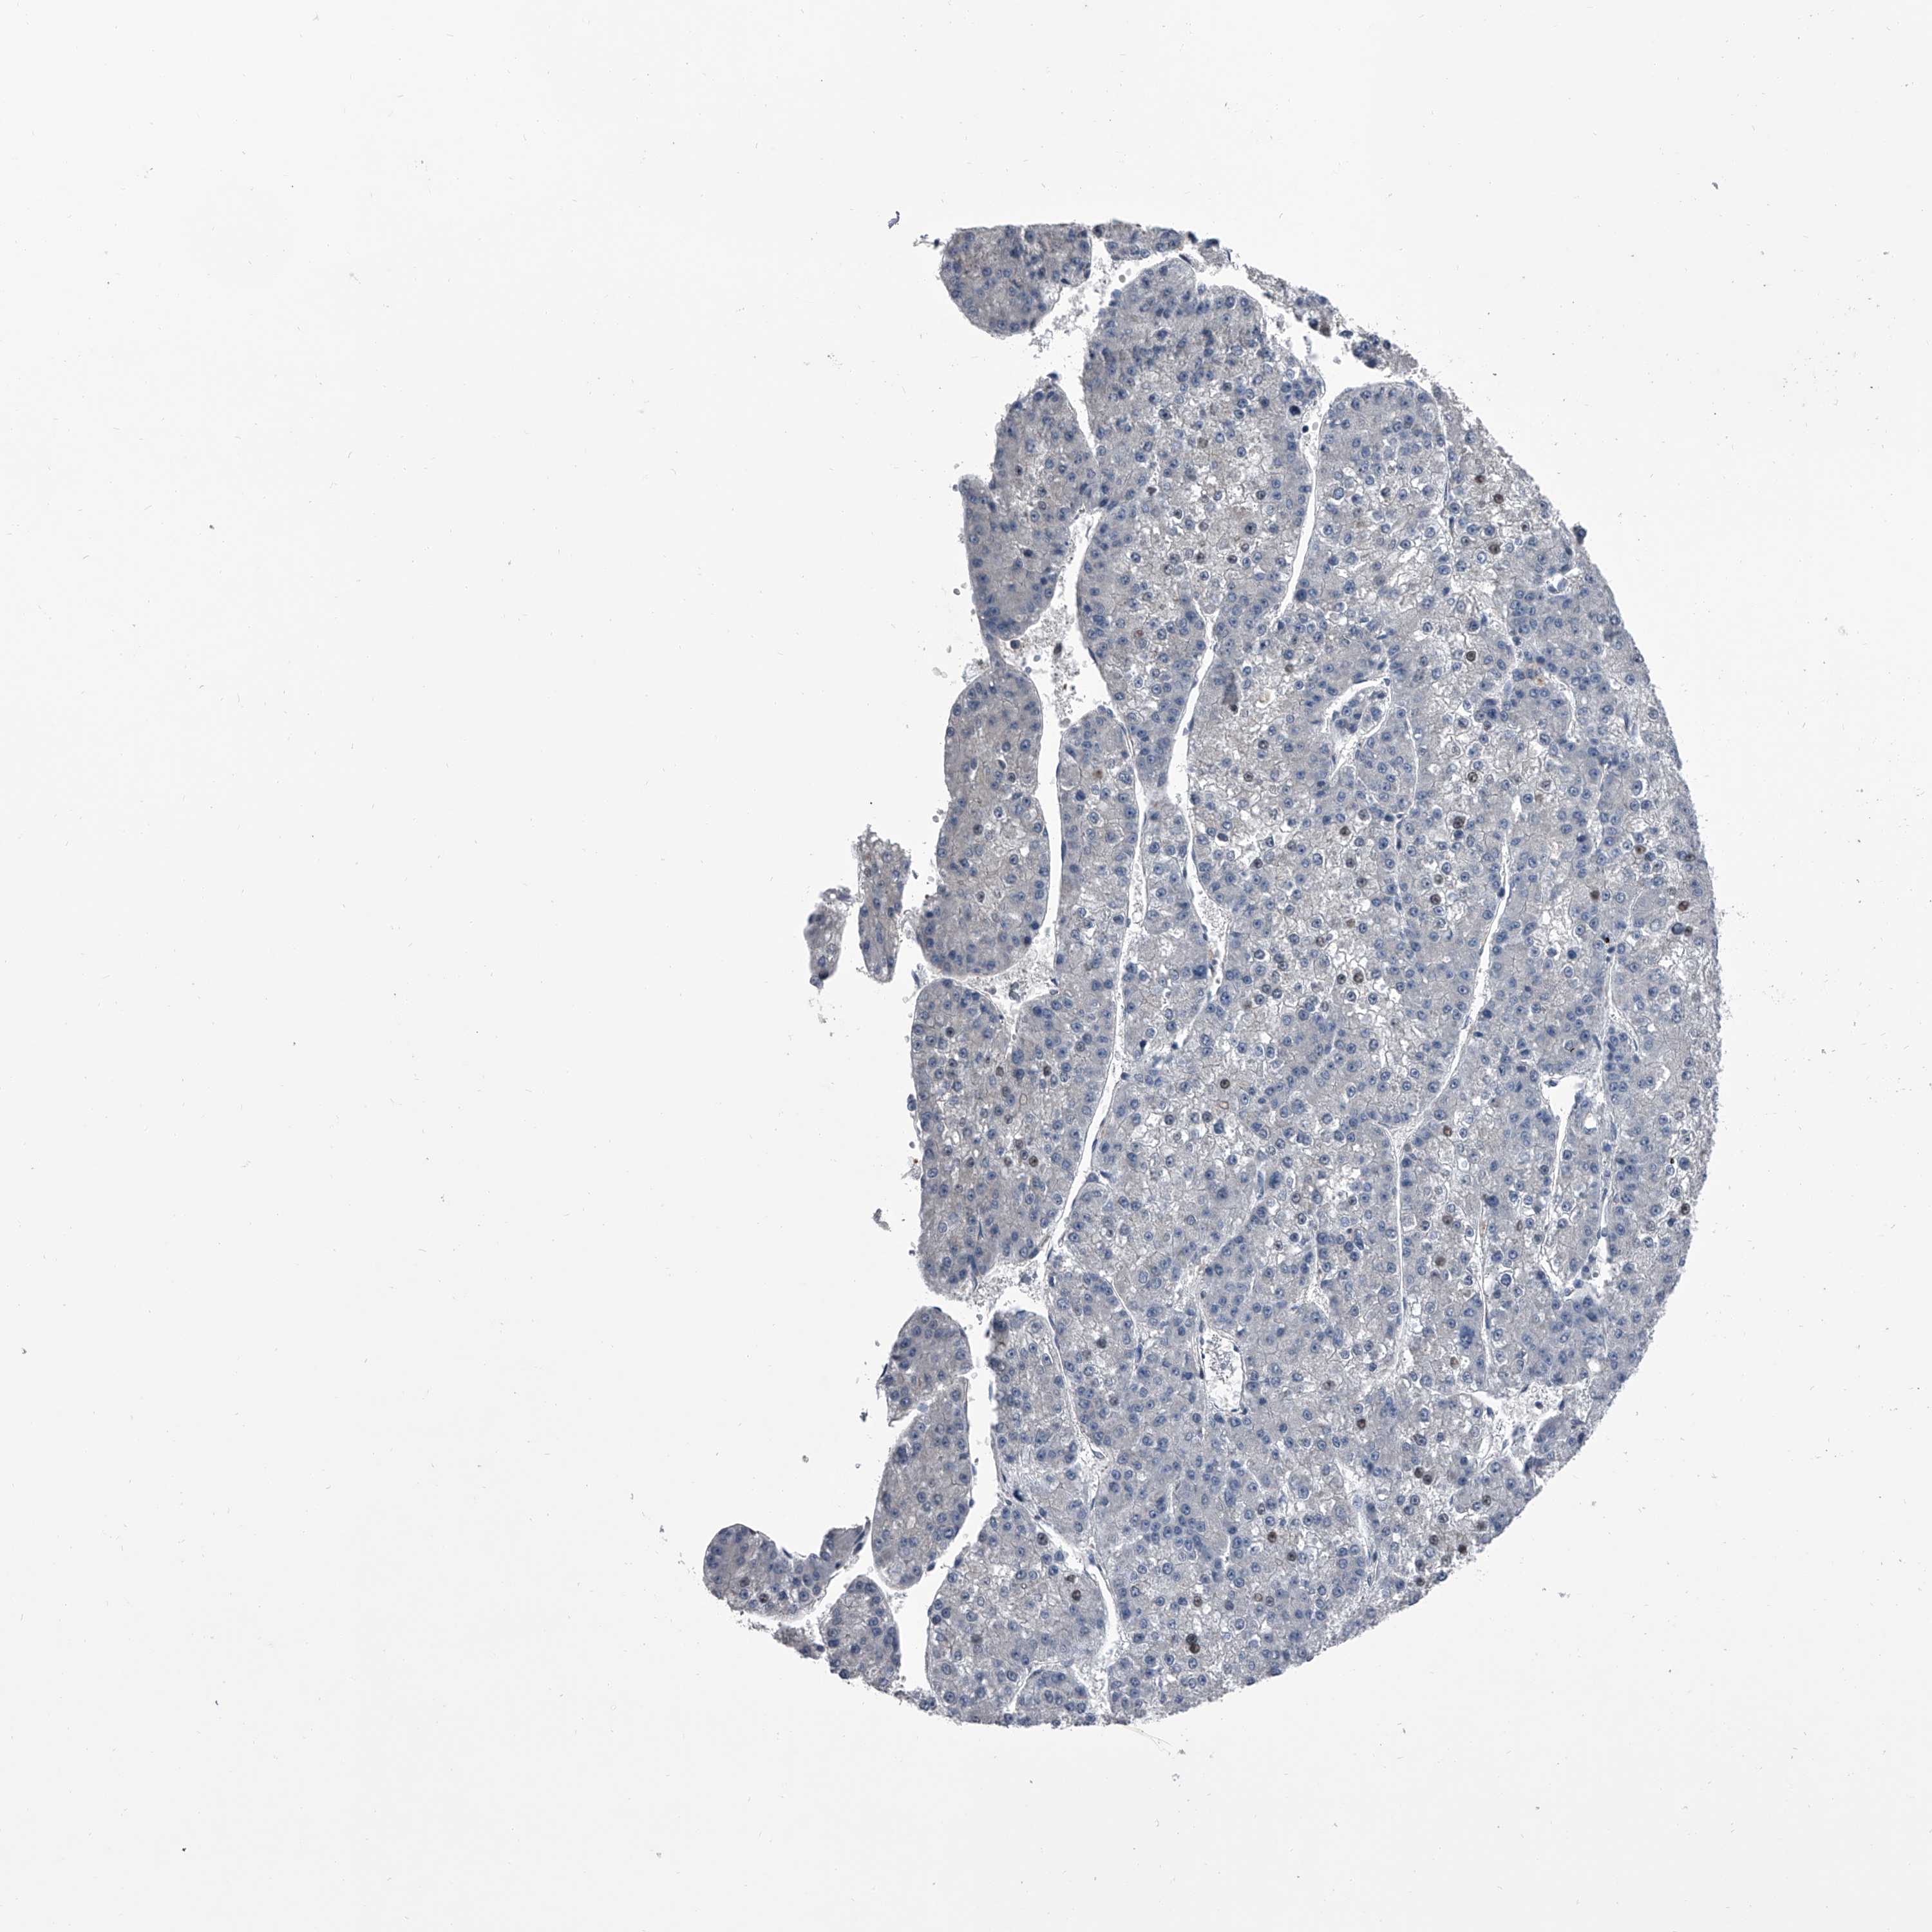

LIVER CANCER - Protein expressioni

A mouse-over function shows sample information and annotation data. Click on an image to view it in a full screen mode. Samples can be filtered based on level of antibody staining by selecting one or several of the following categories: high, medium, low and not detected. The assay and annotation is described here.

Note that samples used for immunohistochemistry by the Human Protein Atlas do not correspond to samples in the TCGA dataset.

Antibody stainingi

Antibody staining in the annotated cell types in the current human tissue is reported as not detected, low, medium, or high, based on conventional immunohistochemistry profiling in selected tissues. This score is based on the combination of the staining intensity and fraction of stained cells.

Each image is clickable and will lead to virtual microscopy that enables deeper exploration of all samples and also displays staining intensity scores, fraction scores and subcellular localization as well as patient and tissue information for each sample.

Antibody HPA029366

Staining

High

Medium

Low

Not detected

Intensity

Strong

Moderate

Weak

Negative

Quantity

>75%

75%-25%

<25%

None

Location

Nuclear

Cytoplasmic/membranous

Cytoplasmic/membranous,nuclear

Cholangiocarcinoma

Carcinoma, Hepatocellular, NOS